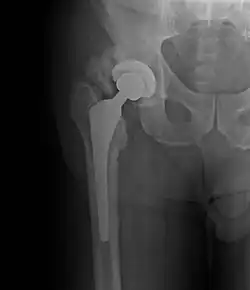

• Locations

• Hip most common - typically after ORIF (52% any grade, 19% Grade III-IV) or THA (43% any grade, 9% Grade III-IV)

Brooker Classification: (radiographic)

• I - islands of bone within the soft tissue (clinically silent)

• II - bone spurs from the pelvis or proximal femur; >= 1 cm gap between opposing surfaces (clinically insignificant)

• III - bone spurs from the pelvis or proximal femur; < 1 cm gap between opposing surfaces (clinically significant)

• IV - ankylosis (clinically significant)